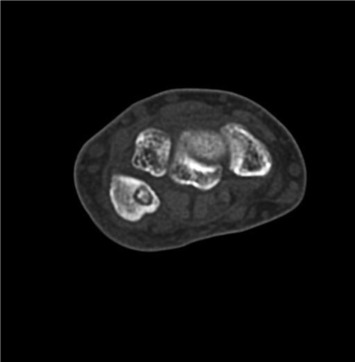

Pain was localized over ulnar styloid and pisiform bone by palpation. Initial X-rays did not detect any abnormality. After 1 month of rest, cold compression and NSAIDs, his complaints were the same and became resistant to NSAIDs. Magnetic Resonance Imaging (MRI) was ordered and signal intensity increase in triangular fibrocartilage complex (TFCC) along with medullary edema of the pisiform was reported. Although conservative treatment was started, the patient did not come back for 8 months. Then, he was admitted again to our institution because of unrelieved pain and progressively decreased ability to use his wrist in daily activities. Anteroposterior, lateral and 30° of supination X-rays (Fig. 1 ) and Computed Tomography (CT) with 3-D reconstruction (Fig. 2 ) revealed a sclerotic lesion surrounded by lucent area in dorsal and radial part of the pisiform suggestive of OO. MRI of the wrist revealed regression of medullary edema of the pisiform and normal appearing TFCC. Open excision and curettage of the lesion was decided.

Fig. 2

Fig. 2.

Transverse section of the pisiform in CT scan before the operation.